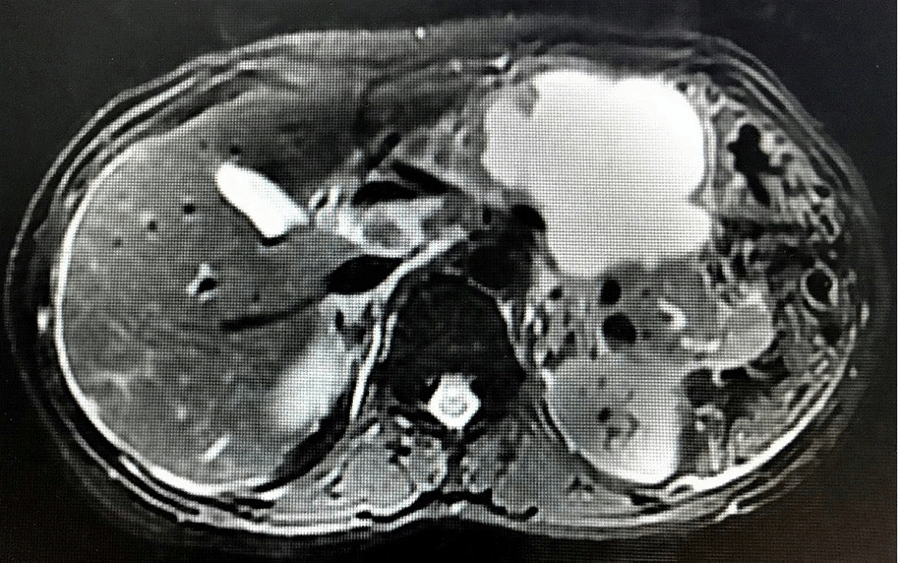

On evaluation, routine hemogram and biochemistry were within normal limits. Serum amylase and lipase were raised three times beyond normal. Pancreas protocol triphasic contrast-enhanced computed tomography (CECT) and contrast-enhanced magnetic resonance imaging (MRI) of the abdomen with cholangiopancreatography (MRCP) showed a large unilocular cystic lesion measuring 8.4 × 6.4 cm with non-enhancing thickened walls in the region of pancreatic neck and body (Figure 1). There was no evidence of calcifications, septations, or mural nodularity. Pancreatic parenchyma adjoining the cyst was atrophic, with some normally enhancing pancreas preserved near uncinate and tail regions. No peripancreatic fat stranding or post-inflammatory sequelae were noted. The main pancreatic duct (MPD) was prominent towards the tail, with no observed communication with the cyst (Figure 2). Multiple necrotic periportal and peripancreatic lymphadenopathy were also noted. A working diagnosis of pancreatitis, secondary to suspected cystic neoplasm of the pancreas, was made.

Figure 2. T2-Weighted MRI Axial Image Showing Cystic Pancreatic Lesion. Published With Permission

Note. Prominent MPD at tail.